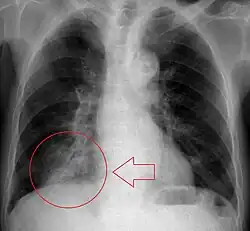

Radiography is the most common form of imaging used in the initial assessment of a foreign body presentation. Most patients receive a chest x-ray to determine the location of the foreign body.[2] Lateral neck, chest, and bilateral decubitus end-expiratory chest x-rays should be obtained in patients suspected of having aspirated a foreign body.[6] However, the presence of normal findings on chest radiography should not rule out foreign body aspiration as not all objects can be visualized.[2] In fact, up to 50% of cases can have normal findings on radiography.[7] This is because visibility of an object depends on many factors, such as the object's material, size, anatomic location and surrounding structures, as well as the patient's body habitus.[13] X-ray beams only show an object if that object's composition blocks the rays from traveling through, making it radiopaque and appearing lighter or white on the image. This also requires it to not be stuck behind something that blocks the beams first.[13] Objects that are radiopaque include items made of most metals except aluminum, bones except most fish bones, and glass. If the material does not block the x-ray beams it is considered radiolucent and will appear dark which prevents visualization.[13] This includes material such as most plastics, most fish bones, wood, and most aluminum objects.[13]

Signs on x-ray that are more commonly seen than the object itself and can be indicative of foreign body aspiration include visualization of the foreign body or hyperinflation of the affected lung.[13] Other x-ray findings that can be seen with foreign body aspiration include obstructive emphysema, atelectasis, and consolidation.[8]